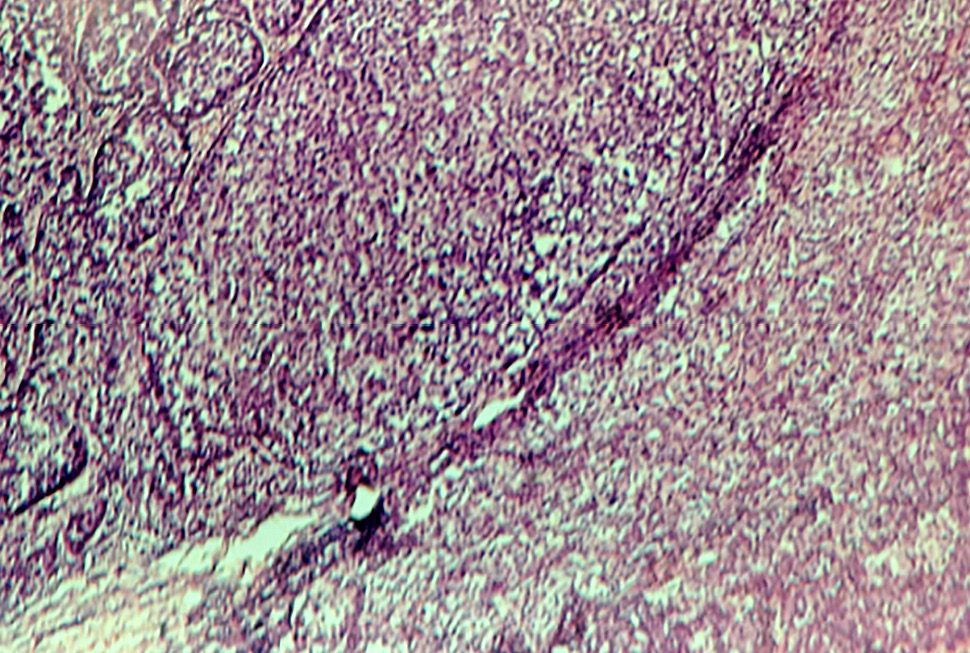

Рис. 3. Гистологическая картина меланомы (окраска гематоксилином и эозином, ×200).

Fig. 3. Histological picture of melanoma (staining with hematoxylin and eosin, ×200).

Гистологическая картина характеризуется распространением опухолевых клеток в сосочковый, сетчатый слои дермы и глубже, а также отсутствием предшествующего радикального роста. В периферических отделах узла поражение эпидермиса распространяется не далее трёх эпидермальных выростов за пределами опухоли (см. рис. 3).

Визуализируются небольшие, умеренно полиморфные опухолевые меланоциты, которые имеют ядра различной интенсивности окраски овальной и округлой формы, узкий ободок розоватой цитоплазмы. Виден также субэпидермальный инфильтрированный рост атипичных меланоцитов в виде крупноальвеолярных скоплений. Толщина по Бреслоу 2,9 мм, митоз 8 мм2. Белки-биомаркеры меланомы S100 и SOX-10 обнаружены с помощью иммуноферментного анализа.